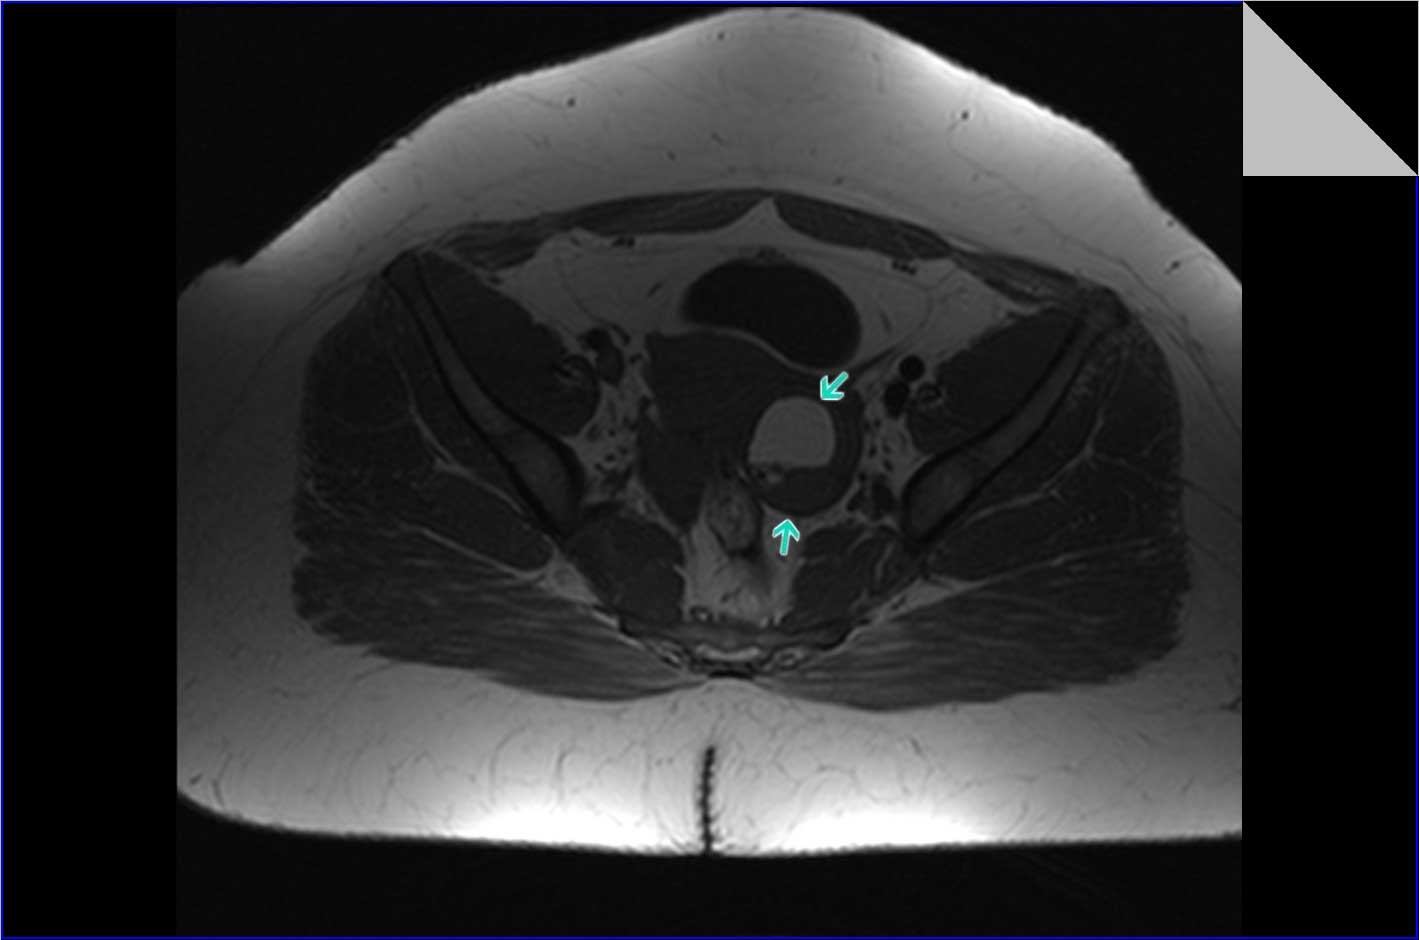

Магнитно-резонансная томография (МРТ) малого таза у женщин является важным методом диагностики различных заболеваний. На фотографиях МРТ можно увидеть органы малого таза, такие как матка, яичники, мочевой пузырь, прямая кишка и другие структуры.

Примеры фото МРТ малого таза у женщин

Ниже представлены примеры фотографий МРТ малого таза у женщин, позволяющие увидеть, как выглядят снимки и какие изменения могут быть обнаружены специалистами.